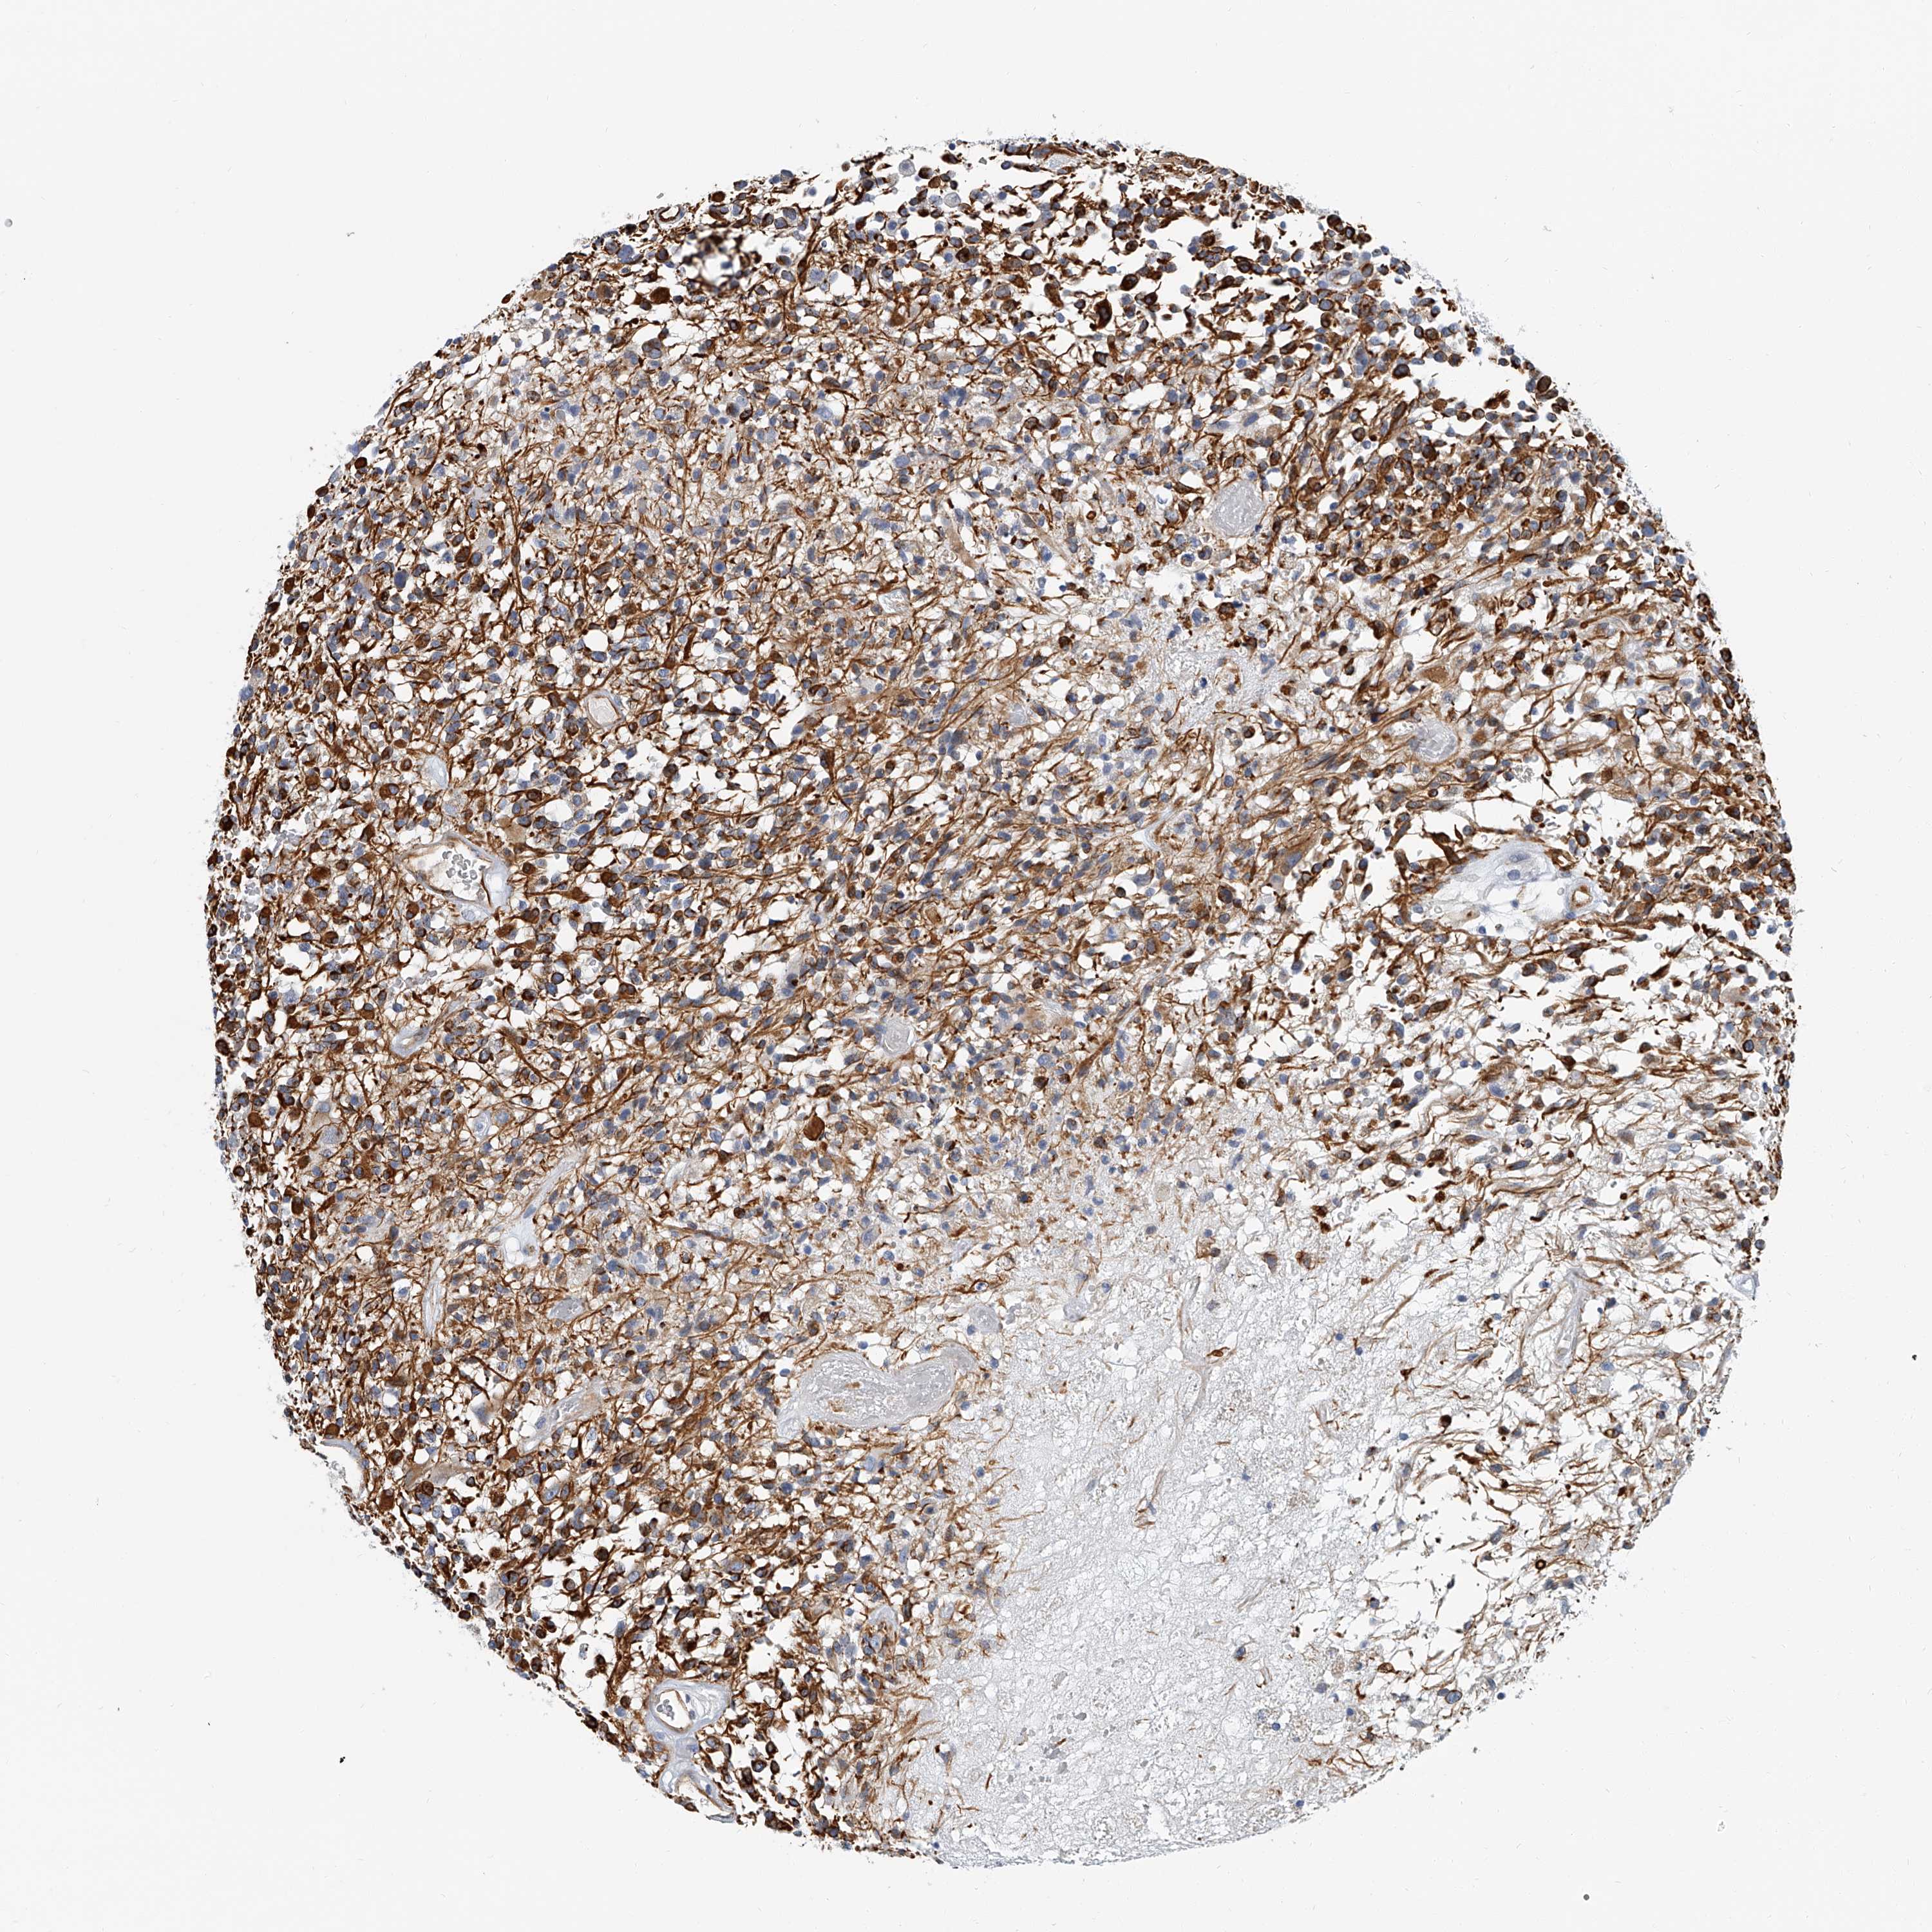

GLIOMA - Protein expressioni

A mouse-over function shows sample information and annotation data. Click on an image to view it in a full screen mode. Samples can be filtered based on level of antibody staining by selecting one or several of the following categories: high, medium, low and not detected. The assay and annotation is described here.

Note that samples used for immunohistochemistry by the Human Protein Atlas do not correspond to samples in the TCGA dataset.

Antibody stainingi

Antibody staining in the annotated cell types in the current human tissue is reported as not detected, low, medium, or high, based on conventional immunohistochemistry profiling in selected tissues. This score is based on the combination of the staining intensity and fraction of stained cells.

Each image is clickable and will lead to virtual microscopy that enables deeper exploration of all samples and also displays staining intensity scores, fraction scores and subcellular localization as well as patient and tissue information for each sample.

Antibody HPA030458

Staining

High

Medium

Low

Not detected

Intensity

Strong

Moderate

Weak

Negative

Quantity

>75%

75%-25%

<25%

None

Location

Nuclear

Cytoplasmic/membranous

Cytoplasmic/membranous,nuclear

Glioma, malignant, High grade

Glioma, malignant, Low grade

Glioblastoma, NOS